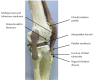

Figure 3. Other conditions that should be considered in differential diagnosis of OSD have been marked over the bone model